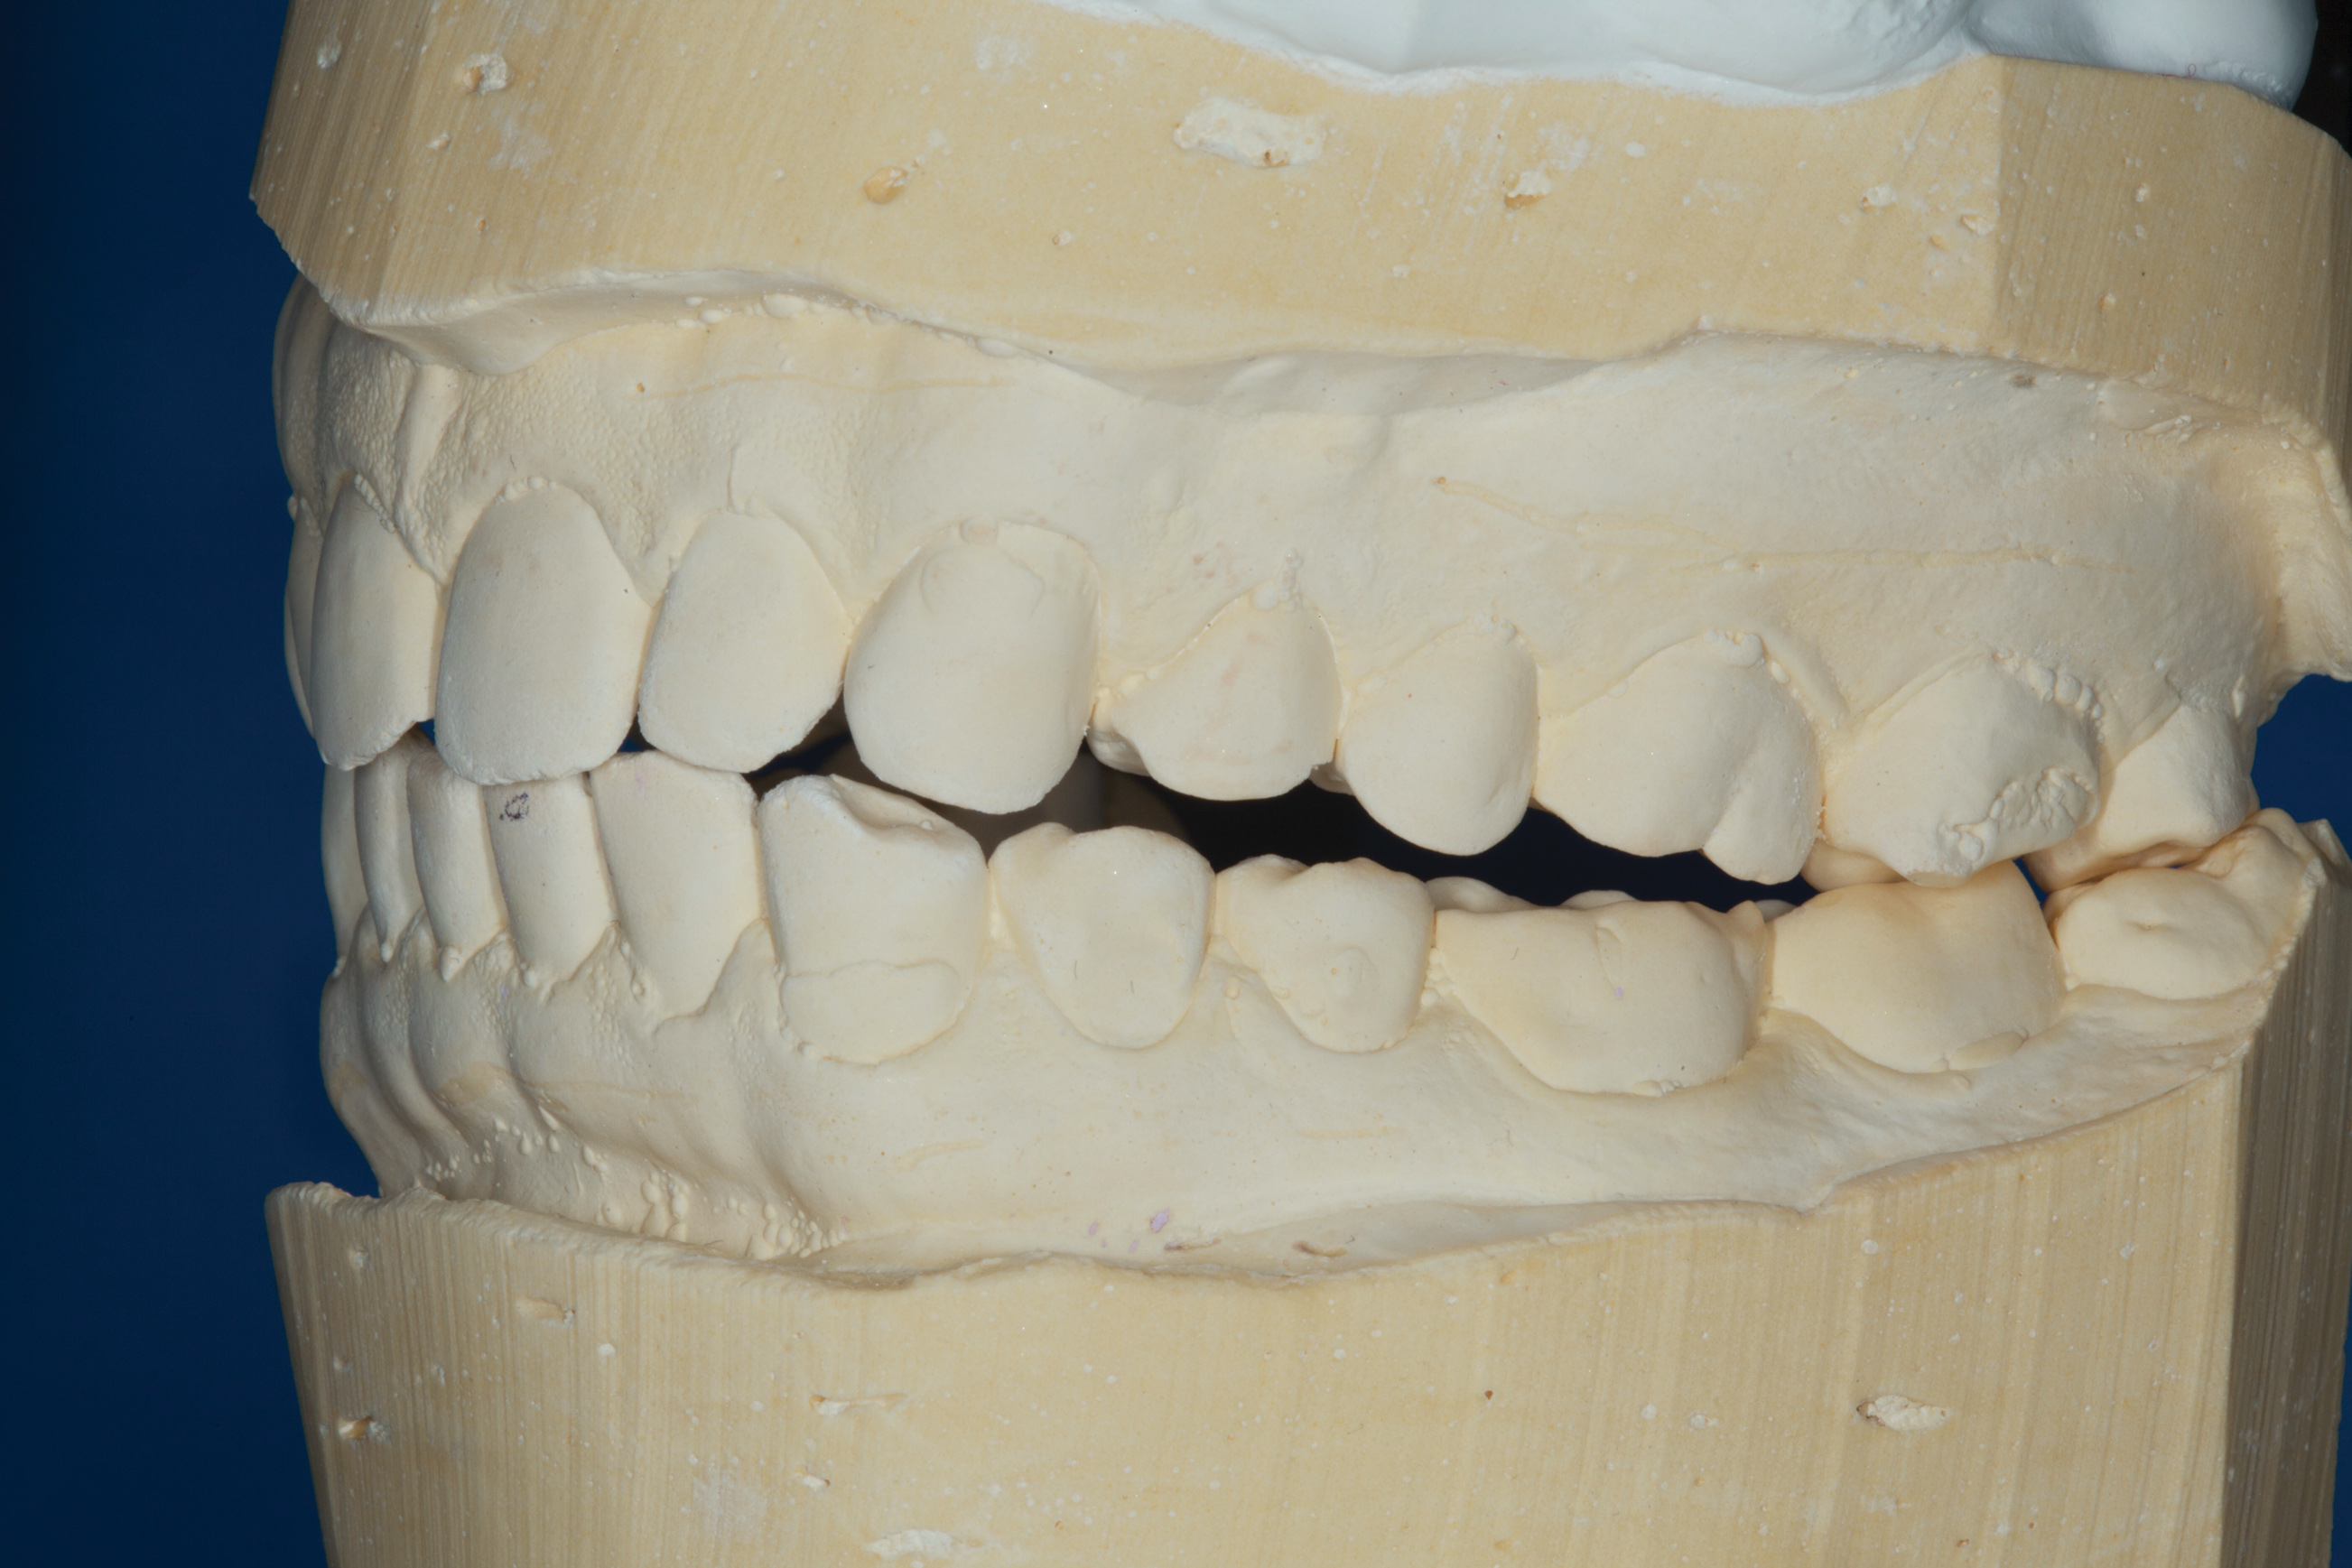

The patient's bite was obviously unsatisfactory, but with the orthotic in place, he was completely symptom-free and stable, and therefore, considered to be in acceptable function. However, he was considered to be in occlusal dysfunction without it because he lacked simultaneous, equal intensity posterior contacts. Deprogramming the patient and confirming centric relation was not considered to be required at this stage because as soon as he removed the orthotic, his occlusal situation was similar to wearing a tripod deprogrammer with only one anterior and two posterior contacts, and these had been confirmed to be reproducible every time when checked intraorally and on the mounted models (Figure 5). The use of a Kois Deprogrammer is one way to obtain centric relation, but other ways, such as bimanual manipulation or the use of a Lucia jig, a leaf gauge, a bite plane, or an occlusal splint have been discussed by various authors.14

Treatment

Accurate vinyl polysiloxane impressions were taken of the upper and lower arches. Two sets of models were obtained and mounted in a semi-adjustable articulator. A diagnostic wax-up to close the posterior open spaces and incorporate the desired esthetic changes was carried out on one of these sets. The posterior waxed-up surfaces were then duplicated with a clear silicon matrix in quadrants. These matrices were loaded with a slightly warmed microhybrid composite and seated onto the corresponding second model, which had been isolated with a separating agent. Warming composites increases monomer conversion, thereby decreasing curing time and shrinkage.18 Once fully cured, the occlusion was adjusted, and the onlays could easily be separated from the models.

(5.) Mounted models showing maximum intercuspation.

Figure 5